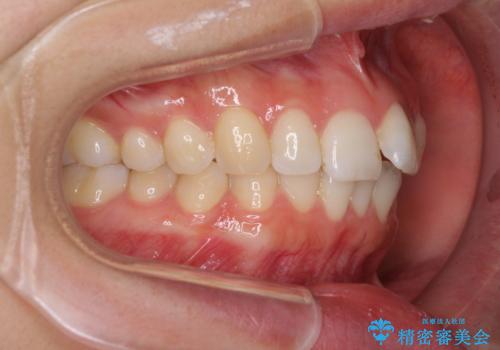

歯列全体の拡大とIPR(歯と歯の間を削る)によってデコボコが解消するようにし、さらにゴムかけを活用して右側の咬み合わせ位置を変えるように設計し、インビザラインにより治療を行うこととしました。

後方移動に際し、上下顎の親知らずは3本とも抜歯することとしました。

結婚式までに前歯を整えたいとのことでしたが、インビザラインでは先に奥歯を移動させてから前歯を動かすため、間に合わない可能性がありました。しかし、結婚式までに期間があったことと、マウスピースをしっかりと装着してくださったことで、十分な歯列に整えることができました。